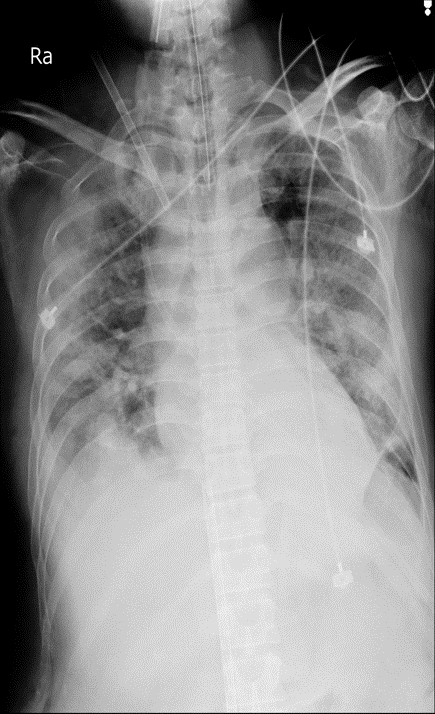

由於患者病情變壞,住院當晚出現嚴重缺氧,經使用呼吸管仍不見改善,隔天胸部出現雙下葉肺部浸潤,動脈血氧和血壓降低,代謝性酸中毒,為嚴重的﹁呼吸窘困症候群﹂。